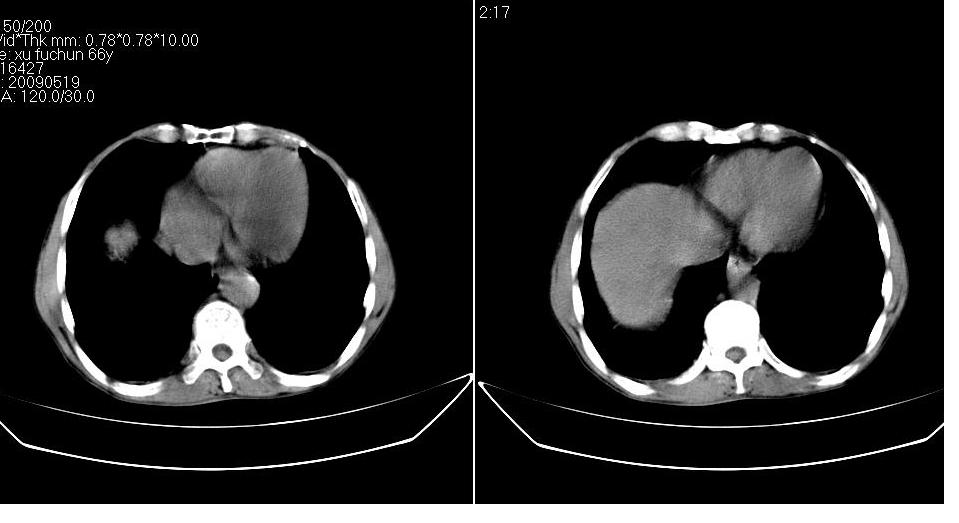

标题: CT20033:上腹部CT平扫

男 66岁,腹疼,b超提示考虑肝癌。

考虑巨块型型肝癌坏死、出血。建议增强。

考虑肝左叶巨块型肝癌可能性大;建议行增强ct扫描。